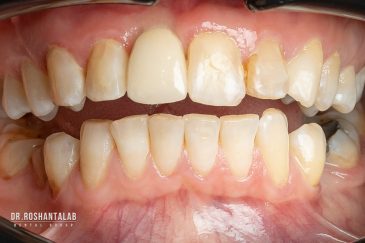

دندانپزشکی زیبایی

طراحی لبخند هالیوودی با متدهای لمینت سرامیکی دندان و کامپوزیت ونیر در کنار اصلاح فرم، خدمات بلیچینگ و روکش دندان، زیبایی چهره شما را تکمیل میکند.ترمیم دندان